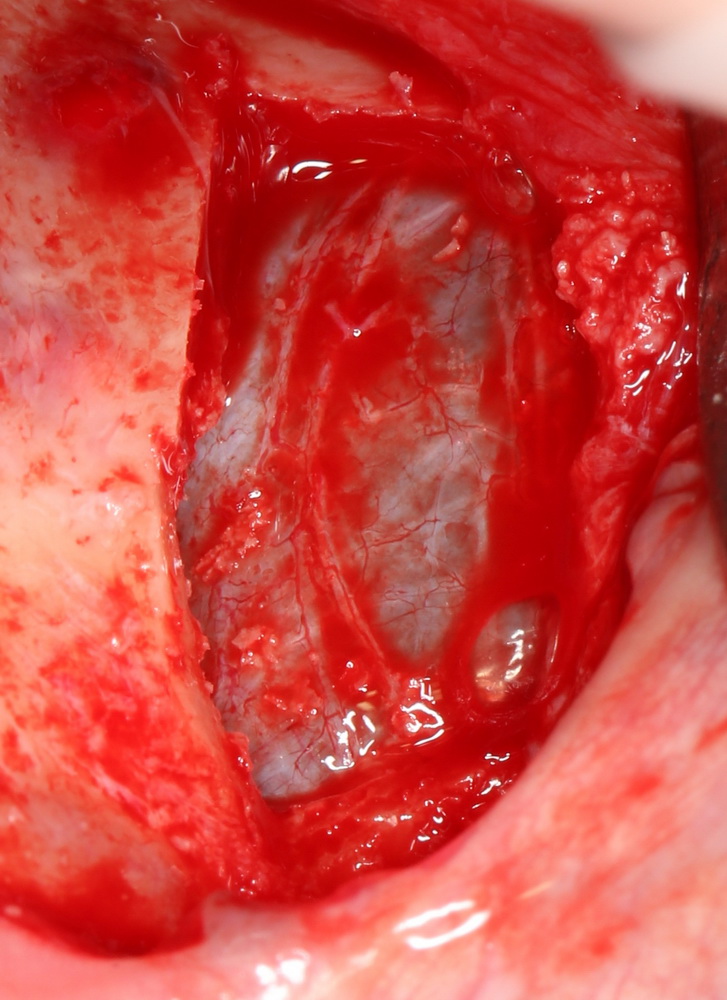

Слизистая оболочка отслаивается до умеренной подвижности (проводится, непосредственно, синуслифтинг), после чего пациента просят сделать несколько глубоких вдохов-выдохов. Во время вдоха неповрежденная слизистая оболочка втягивается внутрь, во время выдоха, наоборот, начинает выбухать. Разумеется, это нужно делать очень осторожно – при слишком тонкой слизистой лучше просто понаблюдать за ней – она колеблется в такт дыханию (рис 60, 61):

Рисунок 60, 61. Контроль отсутствия повреждения слизистой оболочки гайморовой пазухи: слева – вдох, справа – выдох.

Если достаточно отслоенная слизистая оболочка верхнечелюстного синуса не колеблется даже при интенсивных вдохе-выдохе, скорее всего, она повреждена. Первое, что нужно сделать –получить хороший обзор области перфорации. Иногда для этого приходится расширять окно доступа в верхнечелюстную полость, причем весьма значительно. Дальнейшие действия зависят в зависимости от размера и локализации перфорационного отверстия: